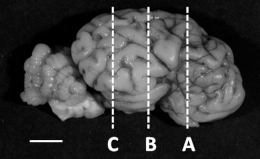

The cerebellum was bisected at the midline of the vermis and the right side processed to paraffin wax and sagittally sectioned at 10 µm. The right cerebrum was cut coronally into 5 mm thick blocks, processed and embedded in paraffin. Sections (10 µm) were cut from three blocks (Level A, B, C, refer to Table 3) and sectioned as previously described [10]. Sections were stained with haematoxylin and eosin (H&E) to assess general morphology. As glucocorticoids play a critical role in myelination [16,17], immunostaining of myelin basic protein (MBP) was performed in both brain regions using immunohistochemistry (IHC) (MBP; Vector Laboratories, Newark, CA, USA; MAB386; 1:400; RRID:AB_94975; [10]). To assess the total area (H&E) and extent of myelination (MBP IHC), scanned sections of each brain region (NanoZoomer, Hamamatsu Photonics, Welwyn Garden City, UK) were converted to grayscale and the threshold was adjusted using ImageJ (NIH). The optical density (O.D.) of MBP staining was measured using ImageJ (NIH). Fields of view within the arbour vitae (cerebellum, n = 10/section), intragyral (cerebrum, n = 10/section) and periventricular white matter (cerebrum, n = 10/section) were sampled. All quantitative analyses were performed with the observer (E.J.C.) blind to the treatment groups.

Morphology of the brain. Data are presented as median (interquartile range, IQR, 25th–75th percentile) from saline (n = 7) and cortisol-infused (n = 6) fetuses at ~130 days of gestational age (dGA). * Significantly different from saline control, p < 0.05, Mann–Whitney nonparametric test (area of cerebrum, level C) or t-test (remaining variables). Below table, left: representative images showing the level (A, B and C) at which the brain regions were sectioned and stained with myelin basic protein (MBP); right: MBP-positive immunostaining of the cerebrum (level B) from a saline and a cortisol-infused fetus. Scale bar left, 1 cm; right, 2.5 mm.